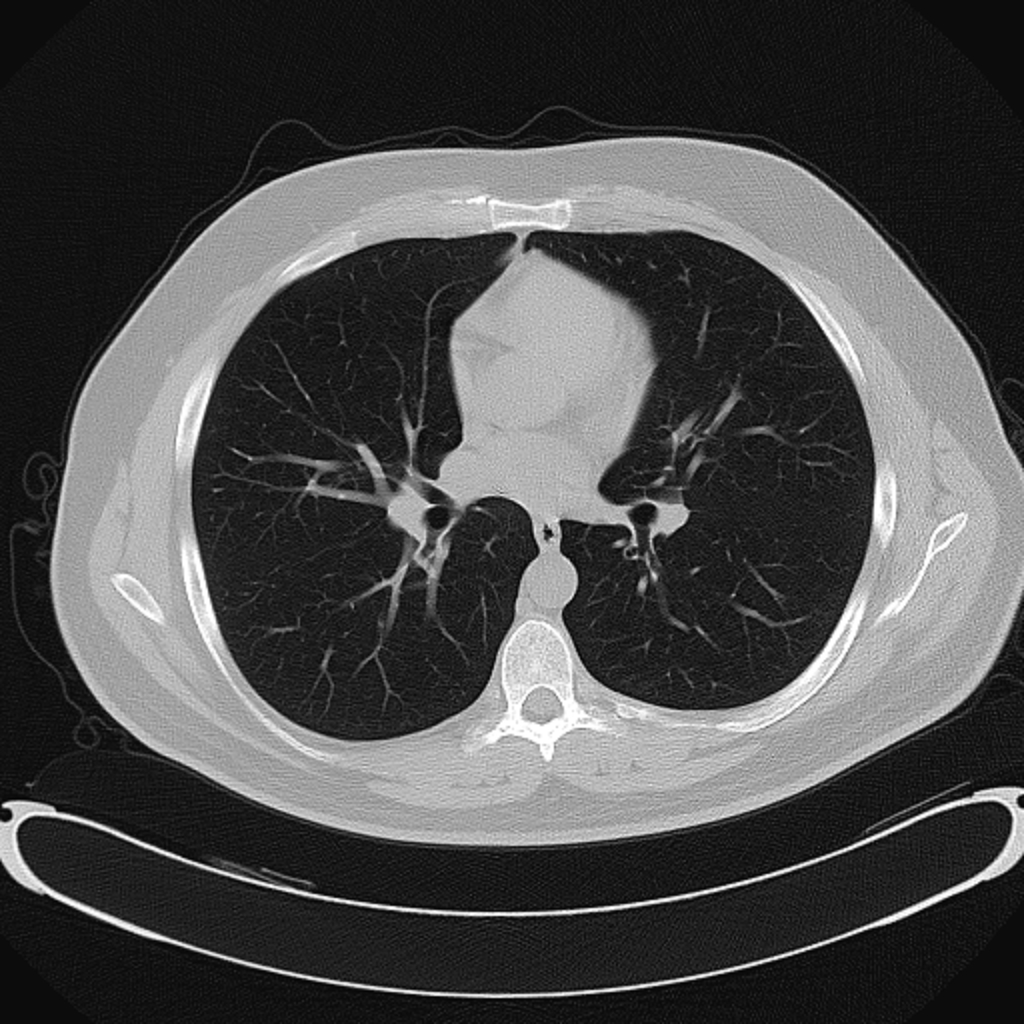

Standard adult chest phantom with lungs, heart, mediastinum, and ribs